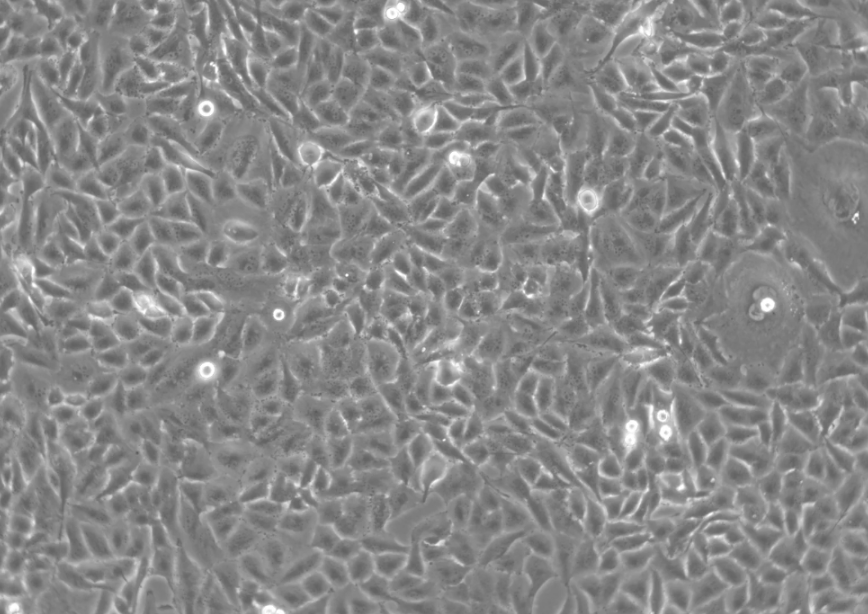

形态 |

成纤维细胞样 |

生长特征 |

贴壁生长 |